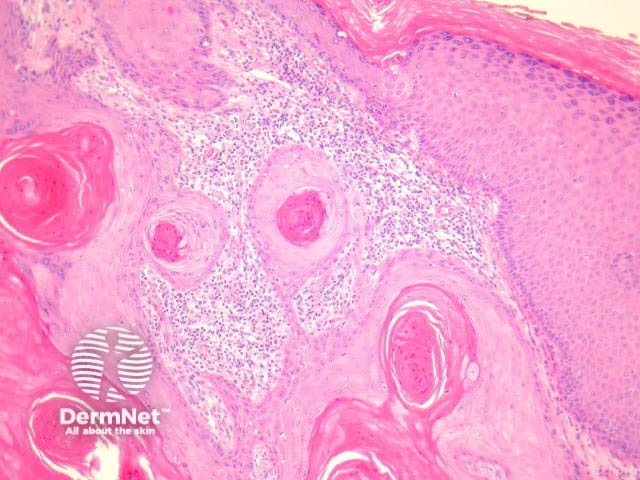

Typical SCC has nests of squamous epithelial cells arising from the epidermis and extending into the dermis (figure 1). The malignant cells are often large with abundant eosinophilic cytoplasm and a large, often vesicular, nucleus. Variable keratinisation (keratin pearls etc) is present (figure 2).

Figure 1